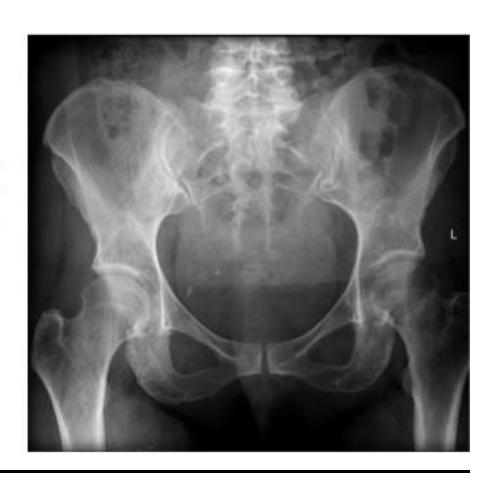

A 15-month-old child was brought to the clinic because of painless limping. There is no history of trauma. The pelvic x-ray is shown.

Q1: Write two abnormalities seen on the X-ray.

- Lateralization of the ossifying centre

- Acetabular angle more than 27ยฐ

- Broken Shenton line

- Shortening of the line from greater trochanter to the horizontal line

Q2: What is the most probable diagnosis?

- Developmental dysplasia of the hip (DDH)